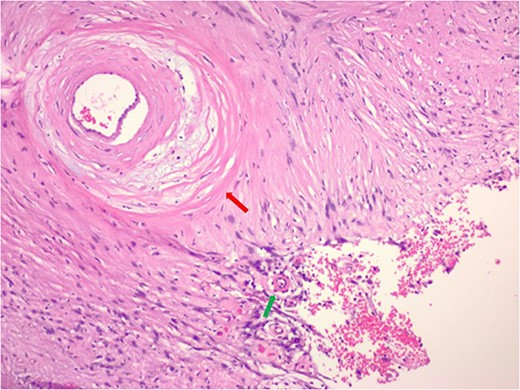

The pathology demonstrated an Ancient Schwannoma (see Fig. 3) with an adjacent ganglioneuroma (see Fig. 4). Because of the benign nature of this tumor, no further workup was required.

Hematoxylin and eosin stain pathologic slide of ancient schwannoma showing hyalinizing vessel (green arrow) and cystic degeneration (red arrow) characteristic of ancient changes.

An ancient schwannoma is a rare diagnosis and comprises ~0.8% of all benign soft tissue masses [2]. Ackerman and Taylor [5] coined the entity of ancient schwannoma by histological diagnosis. Ancient schwannomas typically depict areas of decreased cellularity (loss of Antoni A), hyalinosis of vessels, calcification, areas of fibrosis, stromal edema, hyperchromasia and may have cystic necrosis with evidence of hematoma formation [6]. Its degenerative qualities are primarily attributed to the growth and aging of the tumor which make it “ancient.” The pathology of the tumor arises from the growth phase of the tumor. Prior studies have correlated that as the tumor increases in size, blood flow decreases leading to vascular insufficiency within the tissue and thus degeneration [7, 8].